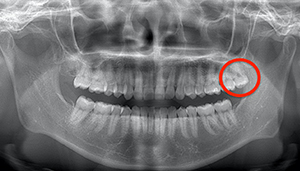

左下の歯茎が腫れている親知らずの症例

- 抜歯前写真(レントゲン、CT等)

左下の親知らず周囲歯肉が腫れていました。

また、手前の歯との間で虫歯もできていました。

3分割して抜歯しました。

| 年齢 | 20代・女性 |

|---|---|

| 主訴 | 左下の歯茎が腫れている |

| 適応するプラン | スタンダード親知らず抜歯プラン |

| 親知らずの生え方 | 歯茎から少し頭が出ている |

| 抜歯時間 | 15分 |

| 費用 | 約7,000円 |

| 抜歯内容 | 下顎の親知らずの抜歯希望の患者様です。 智歯周囲炎となっており、初診時では麻酔が効きづらい旨をお話しし、初診時は抗生物質をお出ししました。1週間後、ある程度歯肉の炎症がとれたことを確認して抜歯を行いました。 麻酔を行い、遠心(親知らずの奥側)歯肉と、手前の歯の頬側の歯肉を切開しました。 歯茎を開いて、手前の歯と引っかかっている部分をカットしました。 その後、骨からでている歯冠部(頭の部分)をカットしました。 その後へーベルで歯根(骨に埋まっている部分)を脱臼し、抜歯を終えました。 切開した歯茎を3針縫って、治療終了となりました。 歯茎を切ったため、3日ほど腫れぼったい感じがあったようですが、痛みはほとんどなく、治癒に向かいました。 |